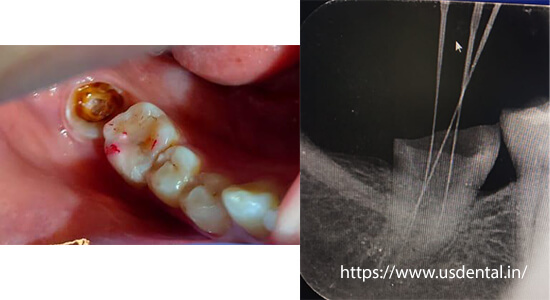

Middle age women reported to the US DENTAL CLINIC with a chief complaint of tooth pain and broken tooth. On a clinical examination it was diagnosed, deep cavity in relation to tooth #47 and it was badly broken due to opposing plunging cusp tip. As it was the second molar, we decided to save that tooth by doing root canal treatment and a crown over it. But tooth destruction was so much that it was finally decided to go for tabletop onlay instead of a full coverage crown.

As it was the second molar, we decided to save that tooth by doing root canal treatment and a crown over it. But tooth destruction was so much that it was finally decided to go for tabletop onlay instead of a full coverage crown.